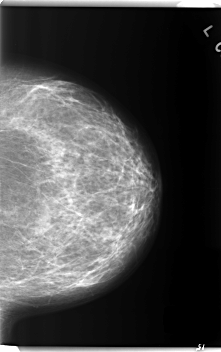

C_0240_1.LEFT_MLO

LEFT_MLO LINES 5976 PIXELS_PER_LINE 3584 BITS_PER_PIXEL 12 RESOLUTION 50 NON_OVERLAY